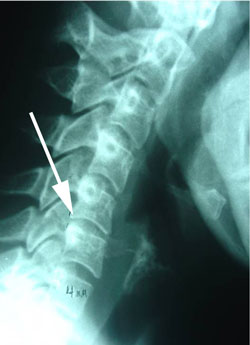

First is a case of a 35 year old female with bilateral arm pain, much worse in the left arm, and severe headaches. The x-ray study and MRI of this patient's spine are here.

retrolisthesis subluxation

Figure 1 shows the cervical spine, or neck, from a side view. At the arrow notice how the vertebra is moved backward on the vertebra below it. This is called retrolisthesis subluxation and occurs because the intervertebral disc between the vertebrae has been torn and sprained to the point that it can no longer hold the vertebrae in normal alignment. Such malpositioning of the vertebra is a clue to the possibility of a disc herniation and disruption inside of the disc to allow the excessive movement of one vertebra on its adjacent segment. Such movement is termed instability.